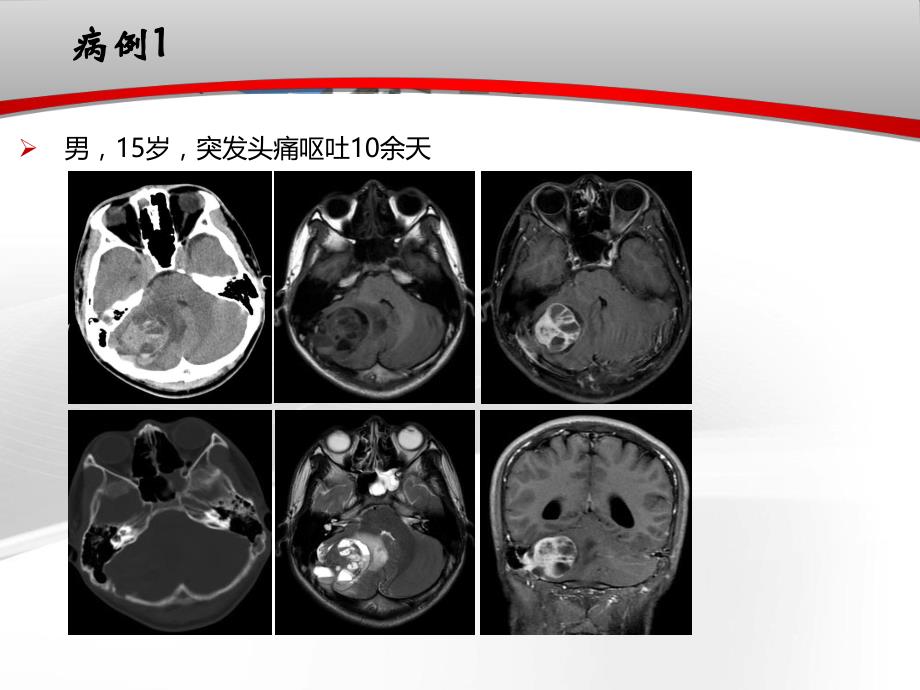

1、病例病例1 1男,15岁,突发头痛呕吐10余天病例病例2 2患者,女,14岁,双侧枕骨无痛性多发肿块2年余概述概述流行病学:仅占骨肿瘤的0.81.8,可发生于任何年龄,也可发生于颅骨任何部位分类:良性肿瘤、恶性肿瘤和肿瘤样病变(或原发性肿瘤、继发性肿瘤和肿瘤样病变)生长方式:外生型、内生型、混合生长型,多于局部形成肿块临床表现:颅骨肿块、肿瘤向颅内生长引起的颅内压增高和局部压迫症状概述概述分类成人以骨瘤最多见,儿童则以骨纤维异常增生症最多见影像学方法:X线、CT、MRI良性恶性肿瘤样病变骨瘤成骨肉瘤嗜酸性肉芽肿血管瘤软骨肉瘤黄色瘤骨母细胞瘤尤文肉瘤骨纤维结构不良症颅骨异位脑膜瘤纤维肉瘤畸形性骨

11、病变区u膨胀性的轮廓是由骨膜的骨再生引起,病变常有细小的骨小梁样结构u肿块内可有不同时期的出血,血液成分的降解和退变导致液平面的形成动脉瘤样骨囊肿原发性颅骨肿瘤样病变原发性颅骨肿瘤样病变鉴别诊断u骨巨细胞瘤:l动脉瘤样骨囊肿好发于20岁以下,而骨巨细胞瘤好发于2040岁患者l动脉瘤样骨囊肿囊变伴出血形成液平面,特别是不同时期的出血的征象出现 概率要远高于骨巨细胞瘤动脉瘤样骨囊肿总结总结颅骨血管瘤1颅骨内异位脑膜瘤2浆细胞瘤3嗜酸性肉芽肿4动脉瘤样骨囊肿5膨胀性骨质破坏高密度的骨针排列明显强化膨胀性改变或溶骨性破坏放射状,针样新生骨形成邻近脑膜强化4050岁多见,周围骨质无硬化肿瘤内部其原始骨板的轮廓仍然可以分辨小儿及青少年单发或多发骨质破坏,边界清楚可见残留骨块,伴或不伴骨质硬化常见于20岁以下偏心、膨胀性、皂泡样骨质病变区液-液平面病例病例1 1男,15岁,突发头痛呕吐10余天病例病例1 1动脉瘤样骨囊肿男,15岁,突发头痛呕吐10余天病例病例2 2患者,女,14岁,双侧枕骨无痛性多发肿块2年余嗜酸性肉芽肿2023-9-1233